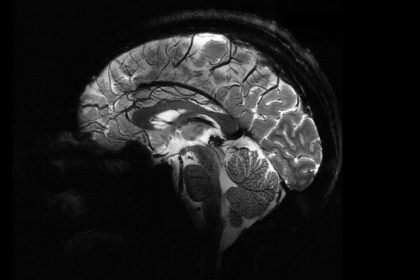

مزیت اصلی این قدرت اضافی این است که میتوان تصاویری با وضوح بسیار بالاتر از مغز را بسیار سریعتر گرفت. تنها در چهار دقیقه، Iseult میتواند تصاویری تا 0.2 میلیمتر از بافت مغز را به صورت افقی، در برشهایی به ضخامت 1 میلیمتر ثبت کند. این حجم معادل چند هزار نورون در یک زمان است.

Iseult چند سال پیش روی کدو تنبل آزمایش شد، اما اکنون اولین مغز انسان خود را که متعلق به 20 داوطلب سالم است، اسکن کرده است. این تصاویر خیرهکننده پتانسیل فناوری جدید MRI را نشان میدهد تا اطلاعاتی را که قبلاً دستنیافتنی بود، در مورد نحوه عملکرد مغز از جمله نحوه رمزگذاری بازنماییهای ذهنی و علائم عصبی مرتبط با خودآگاهی را نشان دهد.